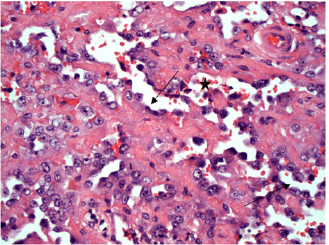

Moderate to marked cellular pleomorphism and nuclear atypia were seen in all cases. Mitoses per 10HPF (2.73 mm2), varied from 3 to 34 per HPF, with case 4 displaying the highest number of mitoses and the only case with metastatic spread (Fig. 4). Solar elastosis was seen in five cases (Fig. 5).

Fig. 5. H&E photomicrograph (100× magnification) of case 2 bulbar conjunctival haemangiosarcoma from a horse characterised by irregularly branching, blood-filled vascular channels. There is evidence of solar elastosis in the conjunctival stroma (arrow).